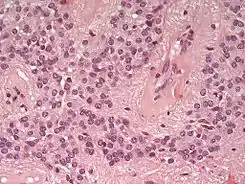

Imagen microscópica de un ependimoma, tinción de H/E

Los ependimomas se componen de células con núcleos regulares y ovoides o circulares. Por lo general se acompañan de una parénquima denso y fibroso haciendo que las células tumorales adopten una forma glandular y elongada que tienen cierto parecido al canal ependimal embriológico con vasos sanguíneos irrigando la neoplasia.[2] Los ependimomas extraespinales o extradurales pueden ser una forma muy inusual de teratoma.[3][4]